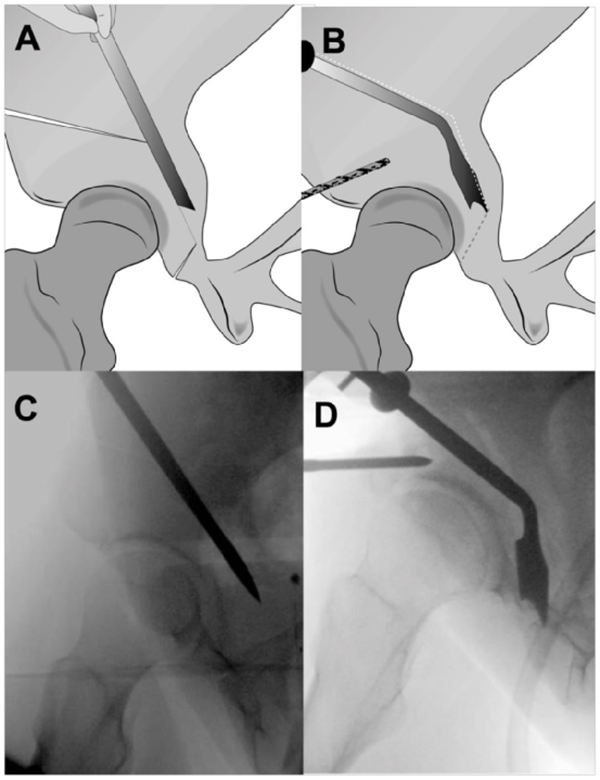

A.图显示用倾斜的Ganz骨刀进行髋臼下截骨。B.后柱的侧视图,显示向坐骨棘倾斜的不完整坐骨截骨。需要多次内侧和外侧击打确认截断整个厚度的坐骨。在截骨过程中伸展下肢,保护坐骨神经

A.耻骨截骨线位于耻骨跟部内侧几毫米处向内倾斜。B.内侧骨撬插入耻骨,近端与远端骨撬插入闭孔,以保护闭孔神经血管束。虚线显示截骨的位置。

A.图示髋臼上截骨,其指向坐骨大切迹,在骨盆缘1cm处停止。B.坐骨截骨,沿骨盆內缘保留后柱截骨。

A.后柱截骨。B.成角骨刀截断残留连接处,截骨块充分游离。C.髂骨斜位透视图显示截骨线。D.游离截骨块